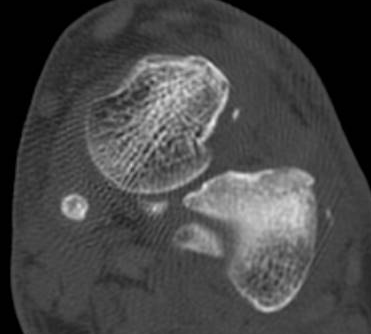

¹ß¸ñ ÇϺνÅÀüÁöÁö¶ì(inferior extensor retinaculum)ÀÇ frondiform Àδë Á¾´Ü¸é°Ë»ç ¹× Á·±Ùµ¿

Ⱦ´Ü¸é°Ë»ç¿¡¼­ °Å°ñ °æºÎ ¿ÜÃø °ß¿­°ñÀý, frondiformÀÎ´ë ½ÉÃþ ¼Õ»ó, ±×¸®°í Á·±Ùµ¿ °æºÎÀδë

(cervical ligament) ÆÄ¿­ÀÌ ÃßÁ¤µÈ´Ù(»çÁø 4, 5).